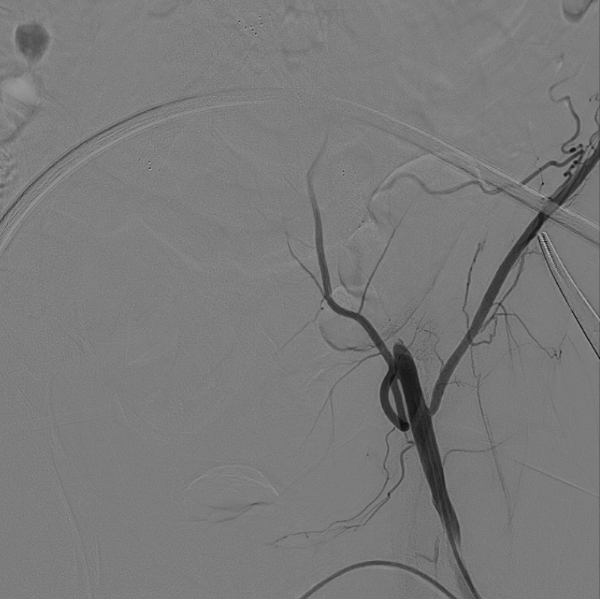

在超声引导下,成功完成双侧股总动脉穿刺。通过导管配合超滑导丝,顺利通过病变区域进入腹主动脉下段,造影明确腹主动脉下段及双侧髂动脉完全闭塞的病变范围与程度。

采用8F Rotarex导管对双侧髂动脉及腹主动脉下段进行减容处理。该器械对于陈旧性血栓具有良好的清除效果,且适用于支架内病变的治疗。减容治疗的主要目的在于获得理想的管腔空间,同时降低远端动脉栓塞的风险。